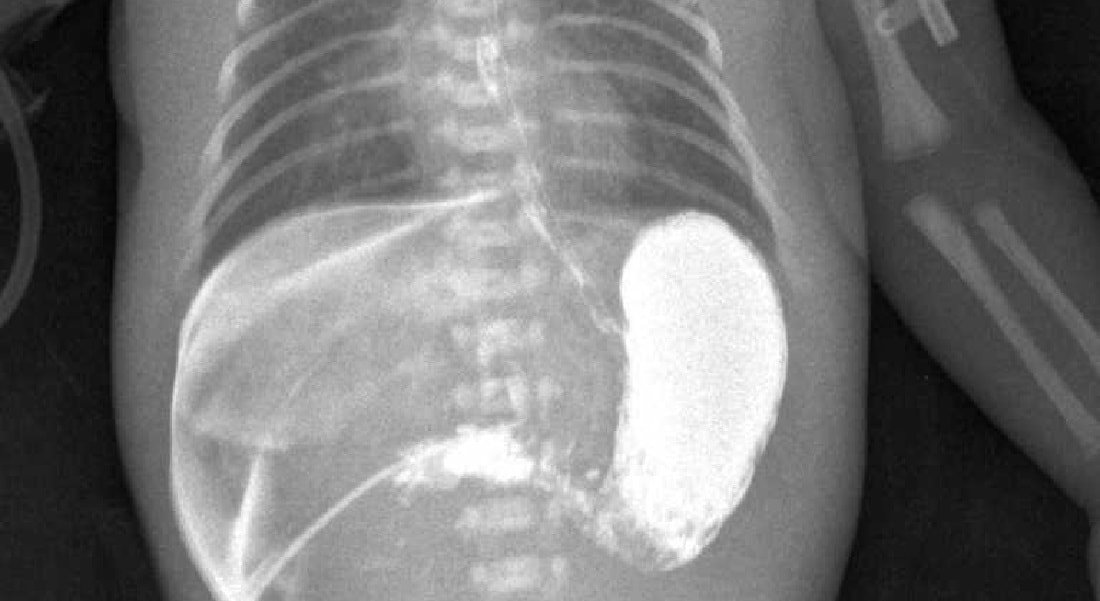

Обязательно диагностика включает проведение гастродуоденоскопии и УЗИ. Делается рентген с контрастным веществом (барием). На снимке видно суженый отдел привратника, на месте мышц прослеживаются плотные тяжи.

Также дополнительным методом исследования является рентгеконтрастирование – пассаж бария по ЖКТ. Хотя рентгенологическое исследование несёт лучевую нагрузку, оно является информативным и позволяет точно определить проходимость привратника. Ребёнку через рот даётся около 30 мл контрастного вещества (5% взвеси бария в или 5% растворе глюкозы). Обзорная брюшной полости выполняется через час и четыре часа, после дачи контраста. При пилоростенозе на снимке будет определяться большой газовый пузырь желудка с одним уровнем жидкости. Эвакуация контраста из желудка в двенадцатиперстную кишку замедлена. После проведения обследования желудок необходимо опорожнить, чтобы при последующей рвоте предотвратить аспирацию бария.

Сужение пилорического отдела нарушает нормальное функционирование пищеварительного тракта и опасно для жизни. На центральном фото внизу виден симптом «песочных часов», когда желудок выпирает в виде двух бугорков

- симптом «песочных часов» – при осмотре живота отчетливо видна перистальтика и два округленных выпячивания с сужением между ними;

При осмотре передней брюшной стенки ребёнка, особенно после кормления, можно увидеть усиленную перистальтику желудка – симптом «песочных часов». Он не всегда явно выражен и чаще встречается на поздних стадиях заболевания.